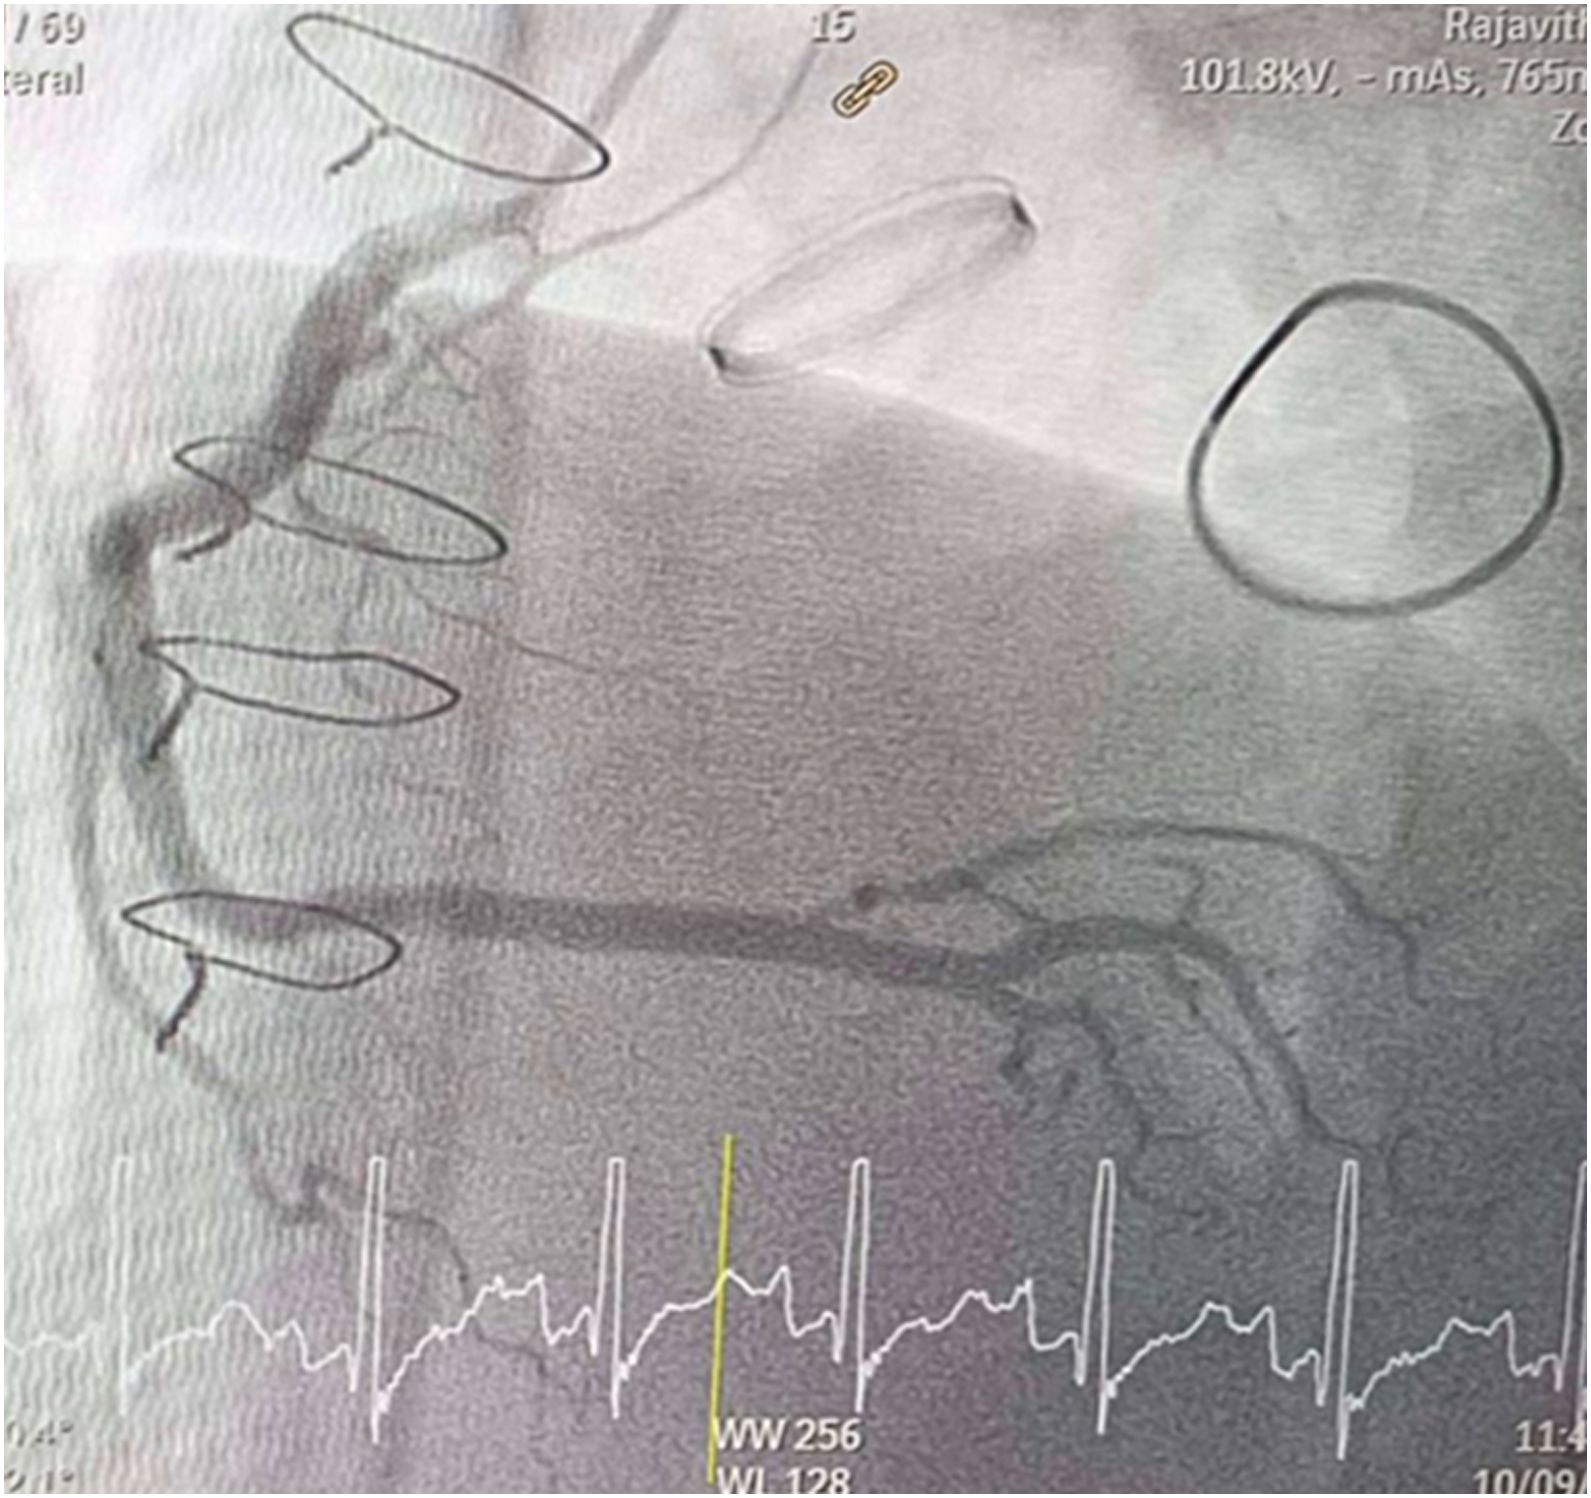

CAG was performed with right femoral approach with JL 4.0/7 Fr, JR 4.0/6 Fr diagnostic catheter showed

Right dominant

LM : mild irregular, non significant stenosis.

LAD : total occlusion mLAD.

LCx : mild irregular, non significant stenosis.

RCA : non significant stenosis.

Inserted Sion wire and thrombuster to LAD revealed multiple red clots.SC balloon 2.0 x 15 mm, then 2.5 x 15 mm, was inflated at mLAD up to 12 atm. IVUS insertion to LAD revealed vessels¡¯ size LM 5-5.5 mm, pLAD 4-4.5 mm, mLAD 3-3.5 mm with intraluminal thrombus, dLAD 2.75-3 mm. Multiple inflations were done at mLAD with SC balloon 2.5 x 15 mm. After multiple SC balloon inflations, the CAG revealed slow flow phenomenon. Then, the operator performed thrombus aspiration, multiple SC balloon 2.0 x 15 mm inflation and gave IC integrillin 3.4 ml. The final angiogram was acceptable result. The anticoagulant was given after CAG. Chest pain was subsided and hemodynamic parameters remained stable. EKG recorded after angiography showed resolution of ST elevation at V1-3. Later, the patient was discharged with warfarin. The Aortomitral intervalvular fibrosa repair surgery was planned due to embolic complication.